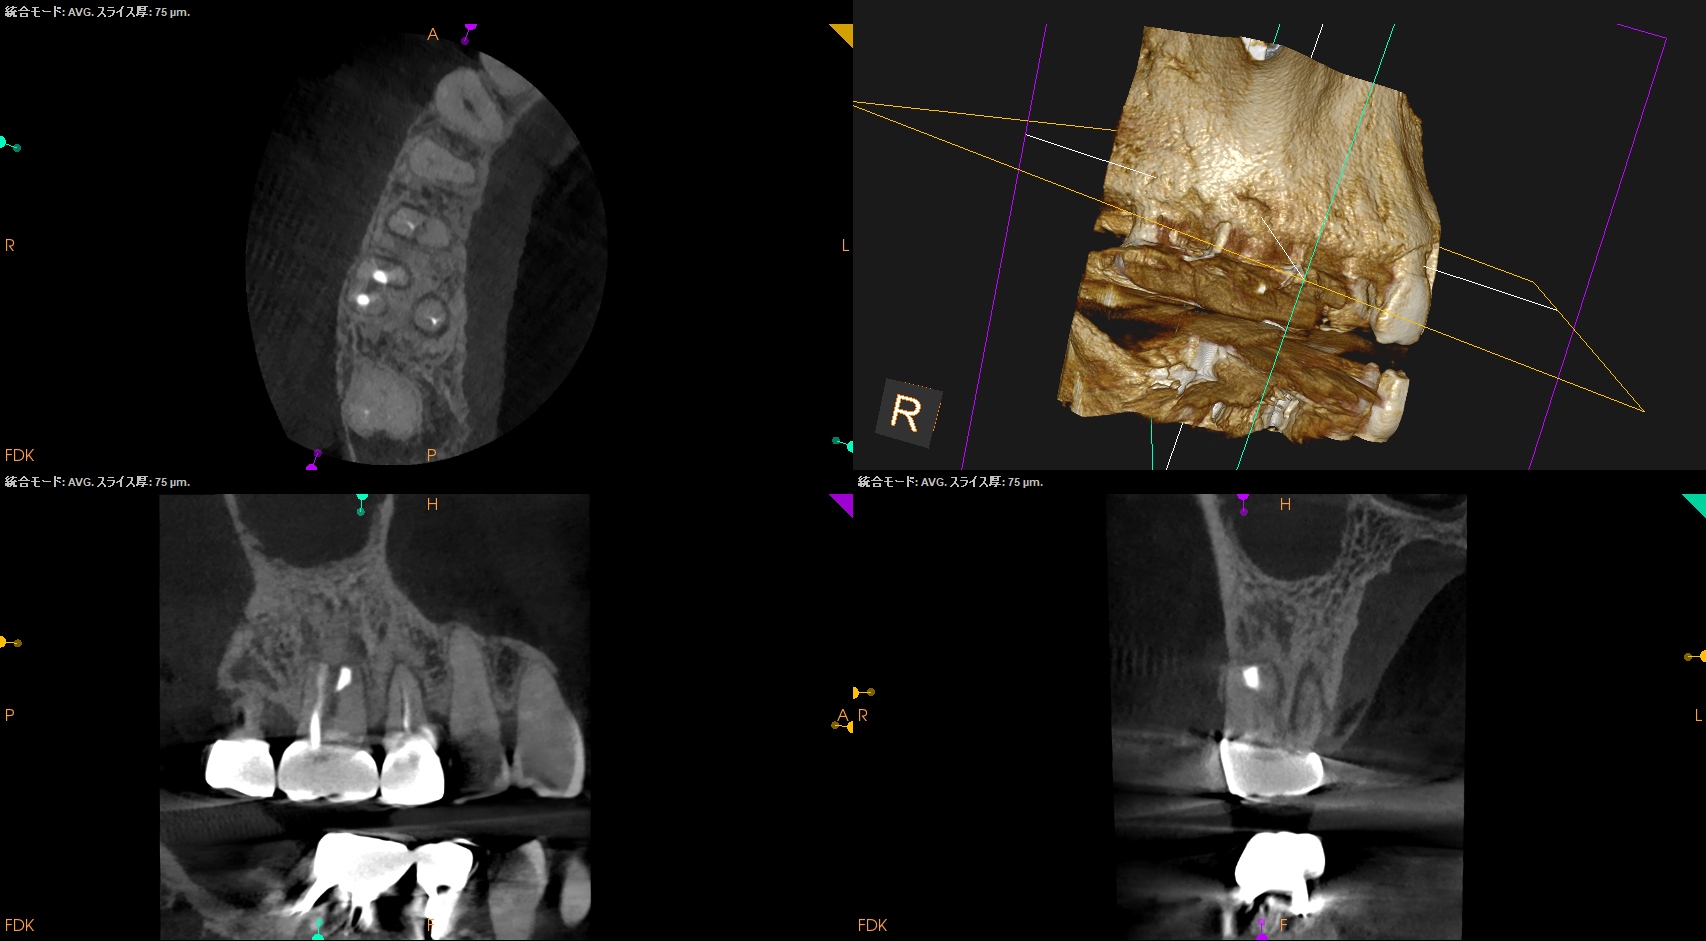

#3 MB,DB Apicoectomy 1yr recall(2025.12.24)

術前のSinus tract・臨床症状(根尖部圧痛)も術後の縫合の傷跡もない。

MB

DB

B

外科治療の際に開創した歯槽骨は再生した。

術前と比較した。

問題は消失した。

MBは根尖部の形成は穿孔しているだろうが即座に穿孔封鎖したから=即座に逆根充したから問題が起きていない。

ということで完治したのでこの日で終診とさせていただいた。